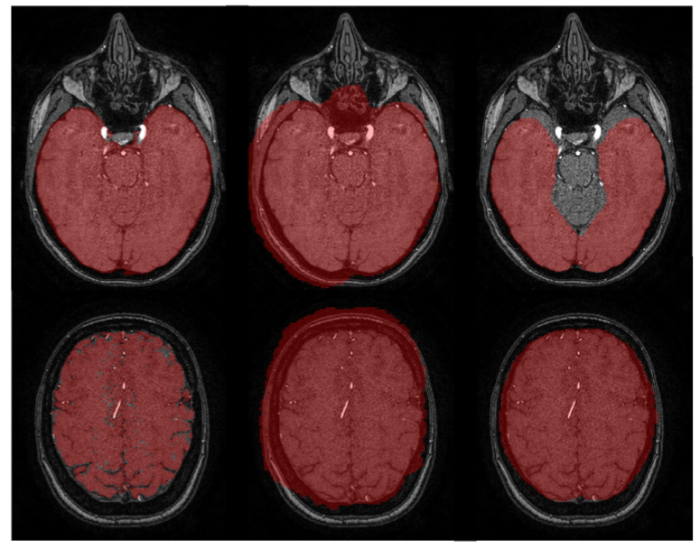

We propose the first joint-task learning framework for brain

and vessel segmentation (JoB-VS) from Time-of-Flight Mag-

netic Resonance images. Unlike state-of-the-art vessel seg-

mentation methods, our approach avoids the pre-processing

step of implementing a model to extract the brain from the

volumetric input data. Skipping this additional step makes our

method an end-to-end vessel segmentation framework. JoB-

VS uses a lattice architecture that favors the segmentation of

structures of different scales (e.g., the brain and vessels). Its

segmentation head allows the simultaneous prediction of the

brain and vessel mask. Moreover, we generate data augmen-